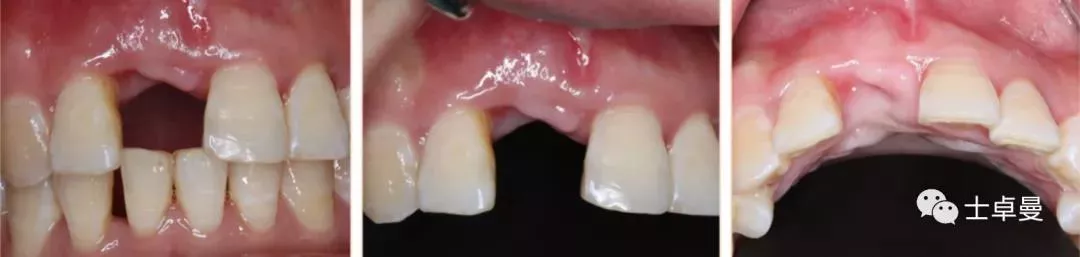

·      ▷ 就诊时检查口内检查

·      11伸长,牙龈呈紫红色,BOP(+),松(Ⅲ);

·      12松(Ⅰ-Ⅱ),21松(Ⅰ-Ⅱ),22松(Ⅱ);

·      牙龈未见明显炎症,余留牙未见异常;

·      咬合正常,低位笑线,中厚龈生物型;

·      牙周系统治疗中,全口卫生状况可,无明显结石,可见少量软垢。